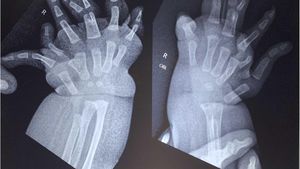

Bayi di India Lahir dengan Banyak Jari Tangan, Ini Penampakannya